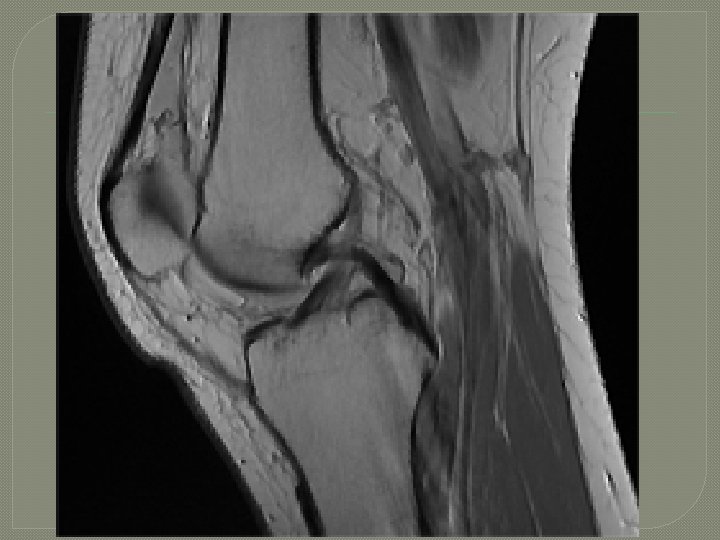

Inside the Knee: ACL

Meniscus Tear Common Injuries Mechanism of Injury Weight bearing with rotational force. Signs and Symptoms Swelling, joint line pain, loss of motion, locking or giving way. Treatment RICE Avascular area: Surgically trimmed and smoothed. Vascular area: Surgically repaired. Prevention Strategies Lower extremity strengthening and conditioning.